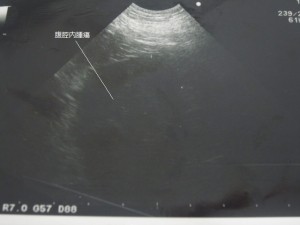

エコー画像です。

脾臓あたりに大きな腫瘤を認めました。